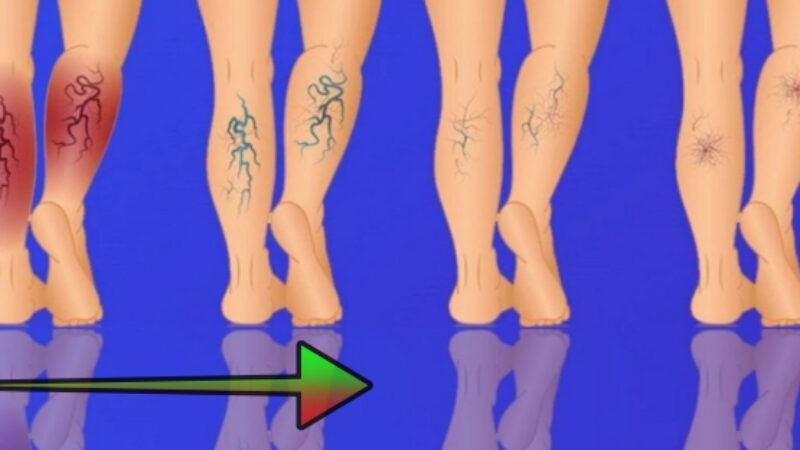

Kŕčové žily sú zapálené žily, ktoré môžu byť mäkké a bolestivé alebo zúžené husté útvary podobné šnúre. Spôsobujú […]

Kŕčové žily sú zapálené žily, ktoré môžu byť mäkké a bolestivé alebo zúžené husté útvary podobné šnúre. Spôsobujú